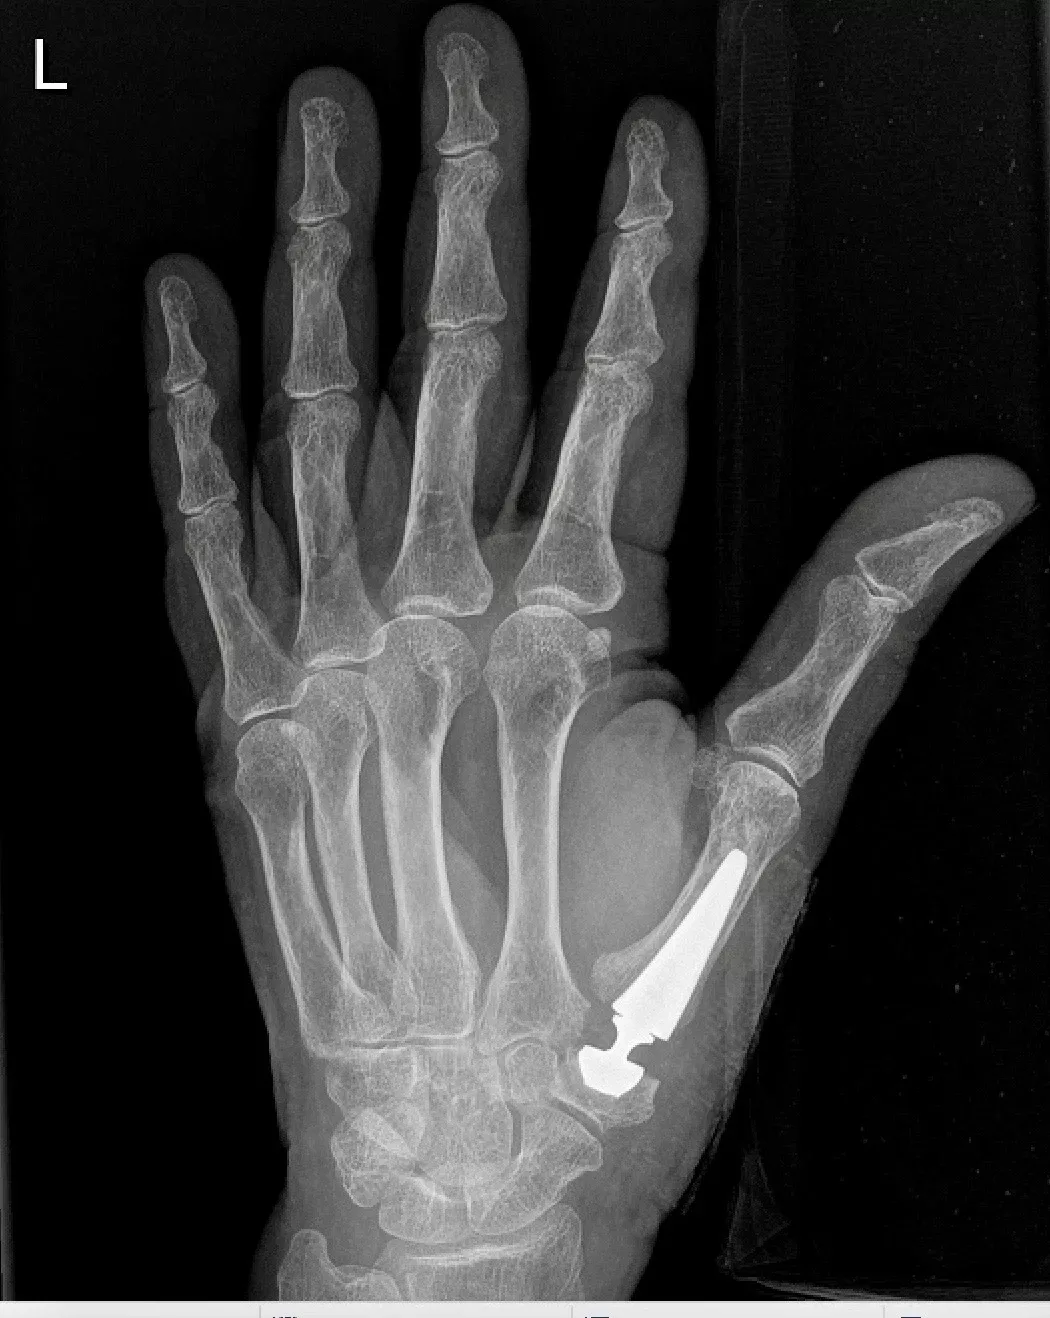

- Duimbasisprothese

- Snelle revalidatie

- Goede pijnverlichting en beweeglijkheid

- Kans op loslating/slijtage is klein

- Indien een prothese niet mogelijk is:

- Andere technieken zoals een Burton-Pellegrini, andere prothesetypes of artrodese

- Ingrepen gebeuren ambulant, meestal onder plexusverdoving